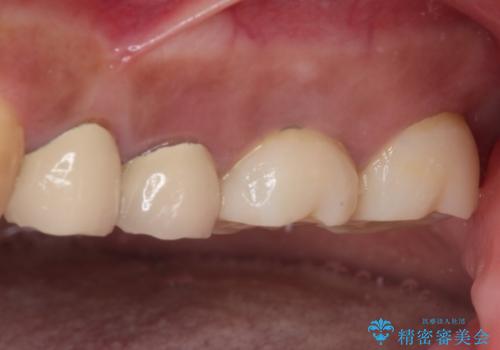

インプラントや歯周外科処置を用いた奥歯の補綴治療

- 下顎の左右奥歯が痛みがあり、噛めないとのことで来院された患者様です。

左右ともに歯根が破折しており、抜歯が必要であったため、抜歯後にインプラント補綴治療を行うこととしました。

左上は当初治療予定ではありませんでしたが、クラウンの周りに汚れがたまっていることが気になってきたため、追加して治療を行うこととしました。

歯肉縁下にまで虫歯が及んでいたため、歯冠長延長術を行い、清掃性の改善を試みます。

治療後は痛みなどなく、快適に噛めるようになりました。